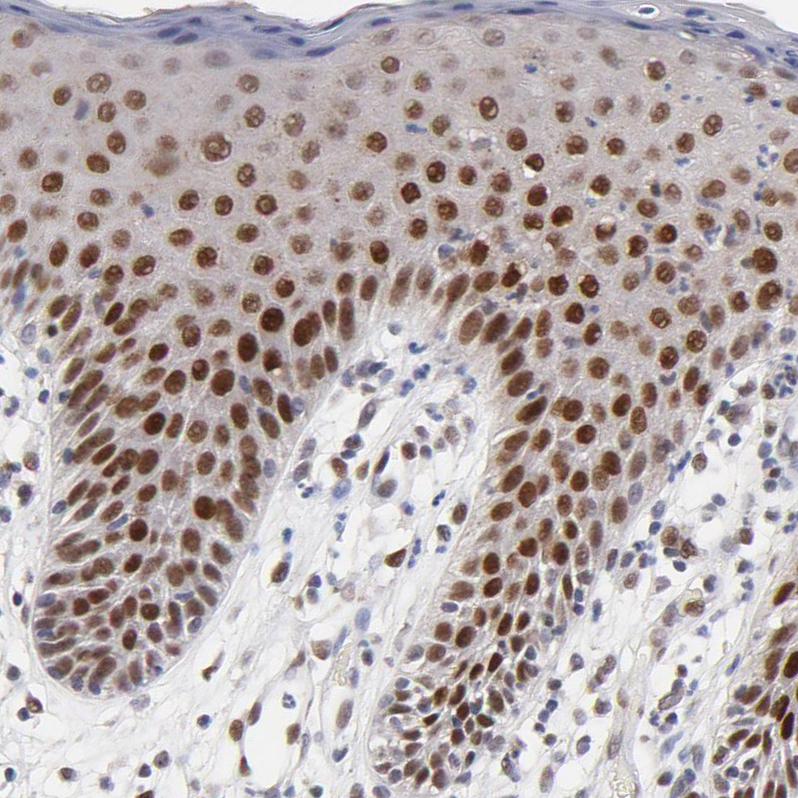

Immunohistochemical staining of human skeletal muscle shows moderate to strong nuclear positivity in myocytes.